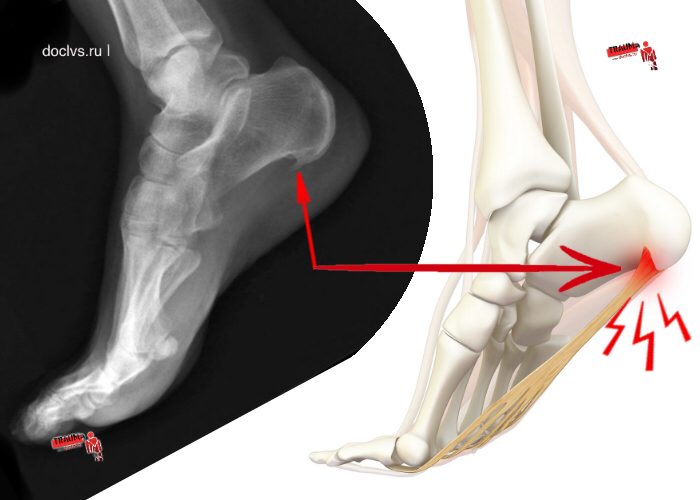

Итак, вот что мы имеем в результате: на пяточной кости внезапно образовался шип, который из себя представляет остеофит.

Остеофит — (от др.-греч. ὀστέον — кость, и φυτόν — растение) — патологический нарост костной ткани на поверхности обычной кости.

Именно этот нарост, прекрасно видимый на рентгене — давит на фасцию под пяточной костью, а именно на сухожилье (под названием — плантарный (подошвенный) апоневроз) и на другие ниже лежащие слои тканей. Такое давления раздражает участки тела, вызывает воспаление и боль, значительно усиливающуюся при долгой ходьбе.